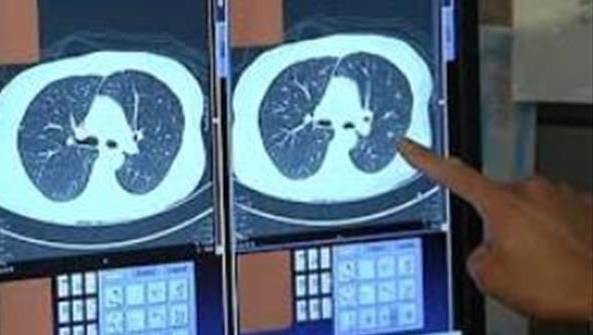

خودش رفت پیش دکتر و شرح حالم رو بدون حضور من داد و دکتر هم برام سی تی اسکن نوشت. دستور دکتر رو داد بهم و گفت:" بلند شو بیا اینجا ! این نوار زردو می بینی؟ همینو برو میرسی به سی تی اسکن."

چند دقیقه ای صبر کردم و جواب سی تی اسکن آمد . دکتر که خودش هم انگار مریض یا بی حال بود ، در حالیکه دستش رو روی سرش گرفته بود، یه نگاهی به صفحه ی مانیتورش انداخت و بعد از بالا و پایین کردن تصویر گفت: "منفیه ، مشکلی نداری برو. "

چهار روز بعد توی سی تی نشون داد!